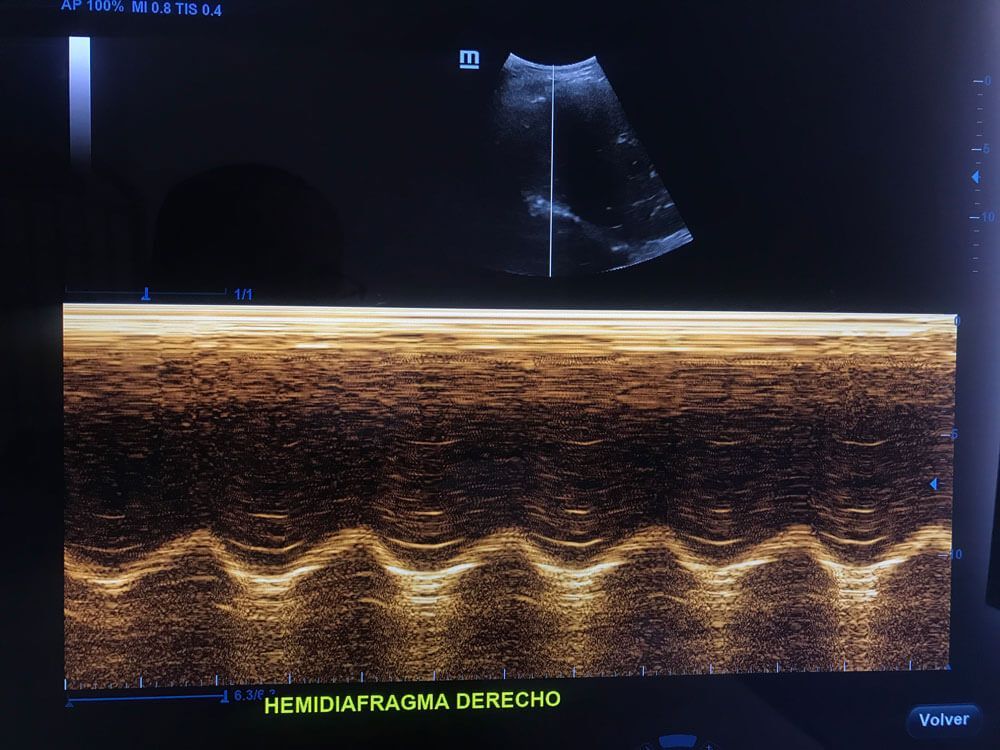

Realizamos

ultrasonidos

convencionales, gestacionales, pediátricos, especializados, entre otros. También aplicamos estudios con